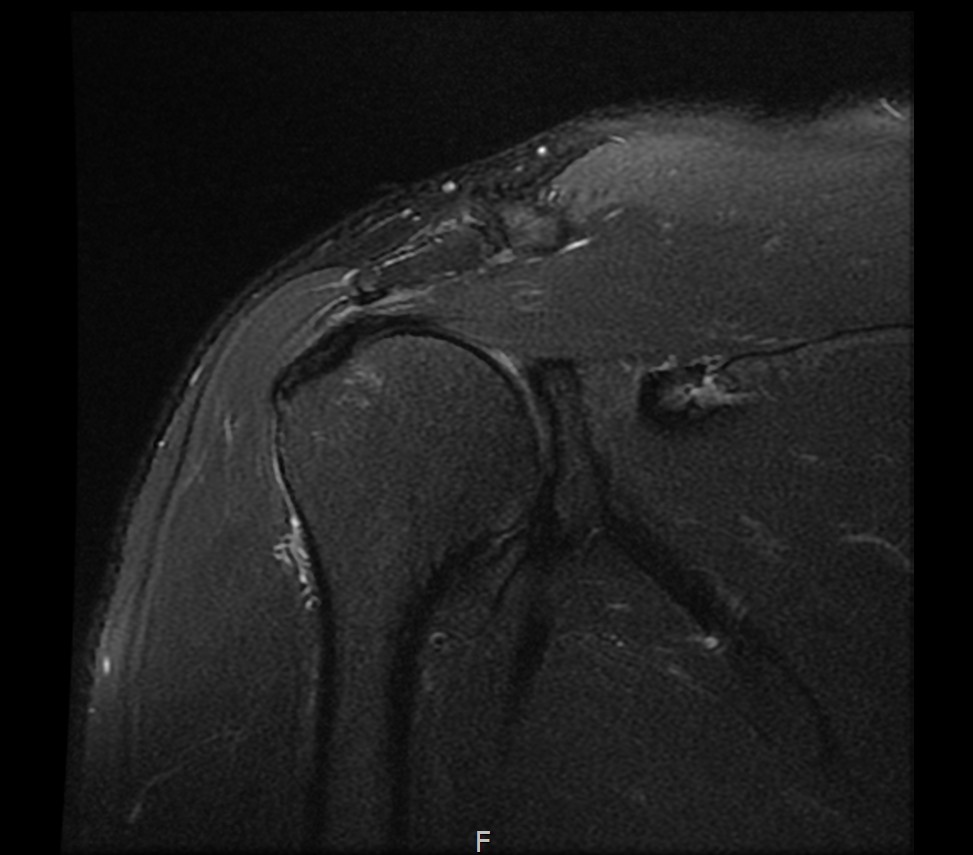

MRI를 검토해보았습니다.

회전근개 극상건의 점액낭면측(bursal-side) 부분파열. 처음보다 파열 범위가 약간 넓어져 있었고, 인대가 얇아진 소견도 보였습니다.

MRI: 극상건 점액낭면측 부분파열

인대 두께: 4.2mm (정상 5~6mm보다 얇음)

6개월 후 MRI: 인대 두께 5.8mm (1.6mm 증가)